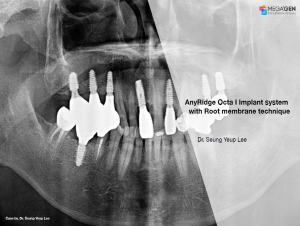

AnyRidge,Dr. Miguel Stanley,Immediate loading,Maxillary Anterior,Scientific background,Single replacement